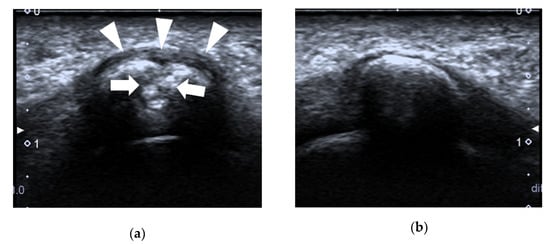

4.3. Morton’s Neuroma

| Morton’s neuroma | intermetatarsal spaces between the 3rd and 4th metatarsal heads | fusiform, hypoechoic mass with “rat’s tail sign” |